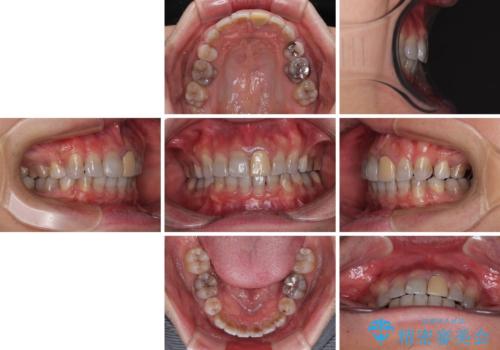

突出した前歯を引っ込める ワイヤー装置での抜歯矯正

- 飛び出した前歯を気にして来院された患者様です。

口元を引っ込めるために上下左右の第一小臼歯4本を抜歯することとしました。

特徴的な歯の色が気になっているとのことで、今後セラミッククラウンによる審美歯科治療を検討されているとのことで、矯正治療の後戻りが落ち着いたタイミングで治療を進めていく予定です。